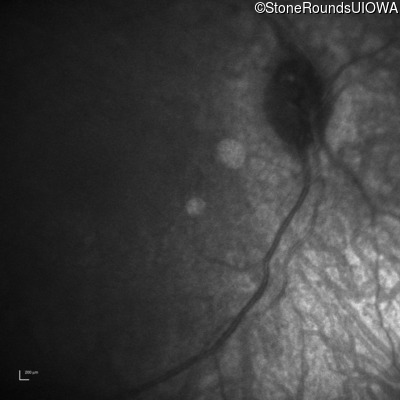

Infrared Fundus Photograph - Right -

No Light Perception

Infrared Fundus Photograph - Left -

Light Perception